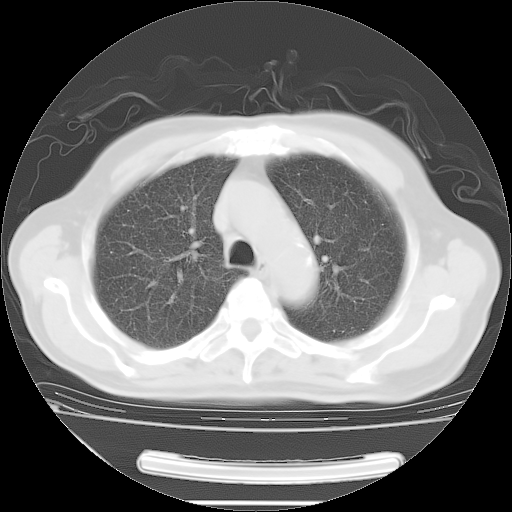

今天复查肺部CT,发现双肺广泛磨玻璃样改变。所以我把3月19日和5月9日相隔50天的肺部CT上传。请大家会诊。

2009年3月19日肺部CT片。

2009年3月19日肺部CT

大致读了系列胸部CT:纵隔窗无明显异常,肺窗:从4、27至今:主要是双肺中下野外带可见毛玻璃样改变,目前处于急性肺泡炎阶段,至于原因考虑1、结替组织或胶原血管性疾病所致?2、恶性疾病如恶组在肺部所致的表现或细支气管肺泡癌?3、药物或其它原因如肺蛋白沉着症所致肺泡炎目前不太可能?总之,明天就去请我院的呼吸科、感染科、血液科和临免专家会诊哈。